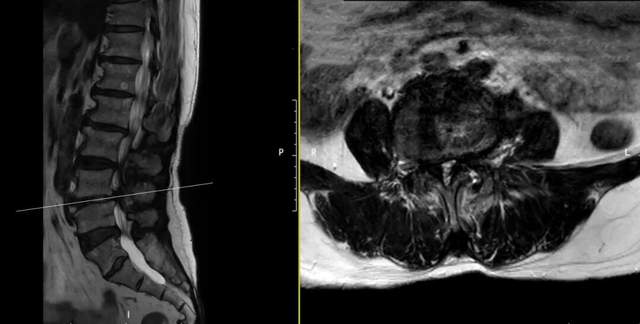

入院MRI检查显示:

○ 腰3/4、腰4/5多节段椎管狭窄,神经根受压严重。